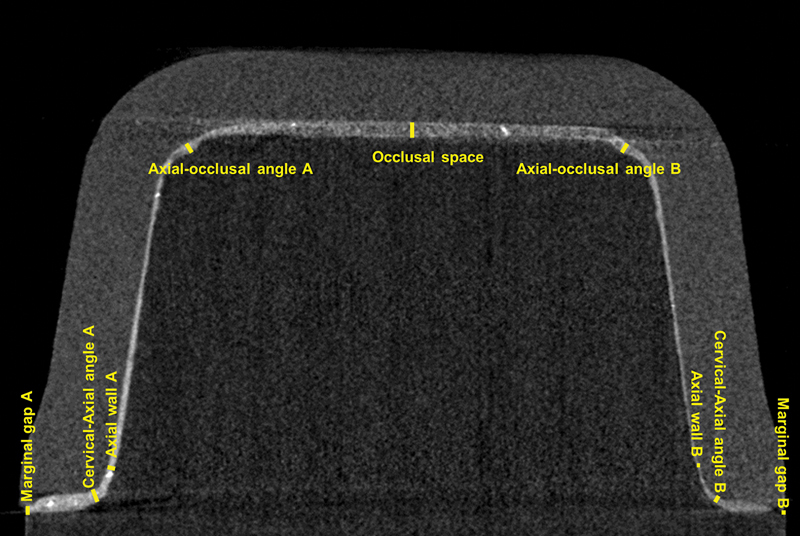

Materials and methods:  Crowns were made considering three factors: IOS (a confocal microscopy-based scanner: TRIOS 3-TR; or a combination of active triangulation and dynamic confocal microscopy: Primescan-PS), milling machines (four-axis: CEREC MC XL-CR or five-axis: PrograMill PM7-PM), and restorative material (lithium disilicate-LD or resin composite-RC) (n = 10). The bonding surface of each crown was treated and bonded to each respective glass fiber-reinforced epoxy resin die using a dual-cure resin cement. A computed microtomography analysis was performed to access marginal/internal gap. The specimens were subjected to a cyclic fatigue test (20 Hz, initial load = 100 N/5,000 cycles; step size= 50 N/10,000 cycles until 1,500 N, then if specimens survived, the step size was increased to 100 N/10,000 cycles).

Results:  TR resulted in a smaller axial-occlusal angle and occlusal gap, and five-axis milling resulted in a smaller marginal gap, axial-occlusal angle, and occlusal gap. Angled points and occlusal surface showed a tendency for overmilling. RC crowns displayed higher survival rates and a more pronounced topography compared with LD independently of the scanning and milling method. LD crowns produced with a five-axis milling machine resulted in higher fatigue performance and rougher topography compared with a four-axis machine.